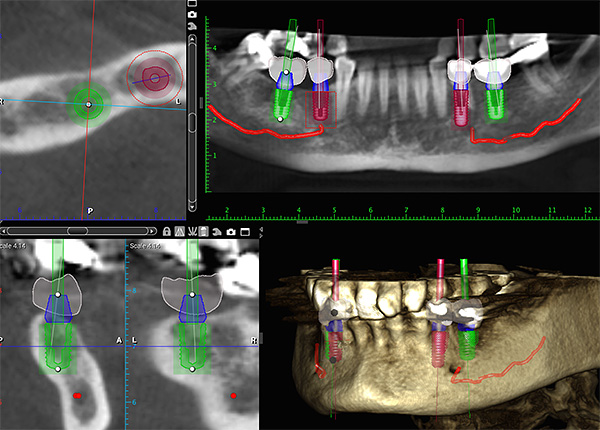

- tomografia computerizzata (TC), che consente di ottenere un'immagine tridimensionale e tridimensionale della mascella (il metodo diagnostico più accurato).

Oggi, nell'odontoiatria avanzata, il software viene sempre più utilizzato per pianificare il processo di trattamento: i dati CT vengono scaricati su un computer, elaborati e il programma aiuta il medico a scegliere il luogo per l'impianto, tenendo conto di tutte le caratteristiche strutturali dell'osso mascellare del paziente. Non è richiesto un pagamento aggiuntivo per questo servizio, poiché è già incluso nel costo dell'impianto, ma tale trattamento sarà relativamente costoso.